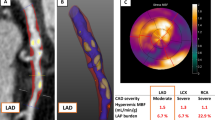

After the acquisition, the QCTA image analysis was performed using previously validated software (QAngio CT Research Edition, version 1.3.6; Medis Medical Imaging Systems, Leiden, the Netherlands) by an experienced reader (V.K. holds a level 3 accreditation by the Society of Cardiac Computed Tomography and is reading CT exams since 2013) blinded to the PET data [9, 10]. This software automatically extracted a 3-dimensional coronary tree and labelled each vessel and segment based on the American Heart Association 17-segment model [9]. The reader confirmed the multiplanar reformation of the vessels and the segmentation by revising the raw 3-dimensional data. The next step was the automatic quantification of all the atherosclerotic lesions of each vessel by the software based on the multiplanar reformation previously approved. For each lesion the analysis provided quantified data, as previously described [9], for the degree of lumen obstruction (lumen diameter, lumen area, lumen diameter stenosis and lumen area stenosis), for the plaque extent (lesion length, plaque volume, mean plaque burden and remodeling index) and for the plaque composition (dense calcium (≥ 350 HU) volume, fibrous tissue (131 to 350 HU) volume, fibro-fatty tissue (76 to 130 HU) volume and necrotic core (low-attenuation, -30 to 75 HU) volume). Consequently the reader picked the tightest lesion per vessel based on the degree of obstruction provided by the QCTA analysis. That was considered the potential lesion of each vessel causing ischemia of the corresponding myocardial territory. Thus, the QCTA analysis was performed on a-per-vessel basis. Figure 1 and Fig. 2 demonstrate two representative case examples.

In total 345 coronary arteries were included, corresponding to 345 myocardial territories with 135 of them (39%) having ischemia on PET. Vessels corresponding to ischemic territories on PET showed worse degree of obstruction as expressed by vessel’s lumen area, lumen area stenosis and diameter stenosis (Table 2). Moreover, these vessels had longer lesions, larger atherosclerotic plaque volume, more extensive plaque burden and showed more positive remodeling (Table 2). Additionally, vessels with flow-limiting lesions showed atherosclerotic plaques with larger volumes of calcium, necrotic core, fibrotic tissue and fibrous-fatty tissue (Table 2). Atherosclerotic plaques causing ischemia had higher percentage of dense calcium (37 ± 22% vs 28 ± 22%, p = 0.001) and lower percentage of fibrous-fatty tissue (9 ± 8% vs 14 ± 11%, p < 0.001) compared to vessels without flow-limiting lesions (Figs. 1, 2).